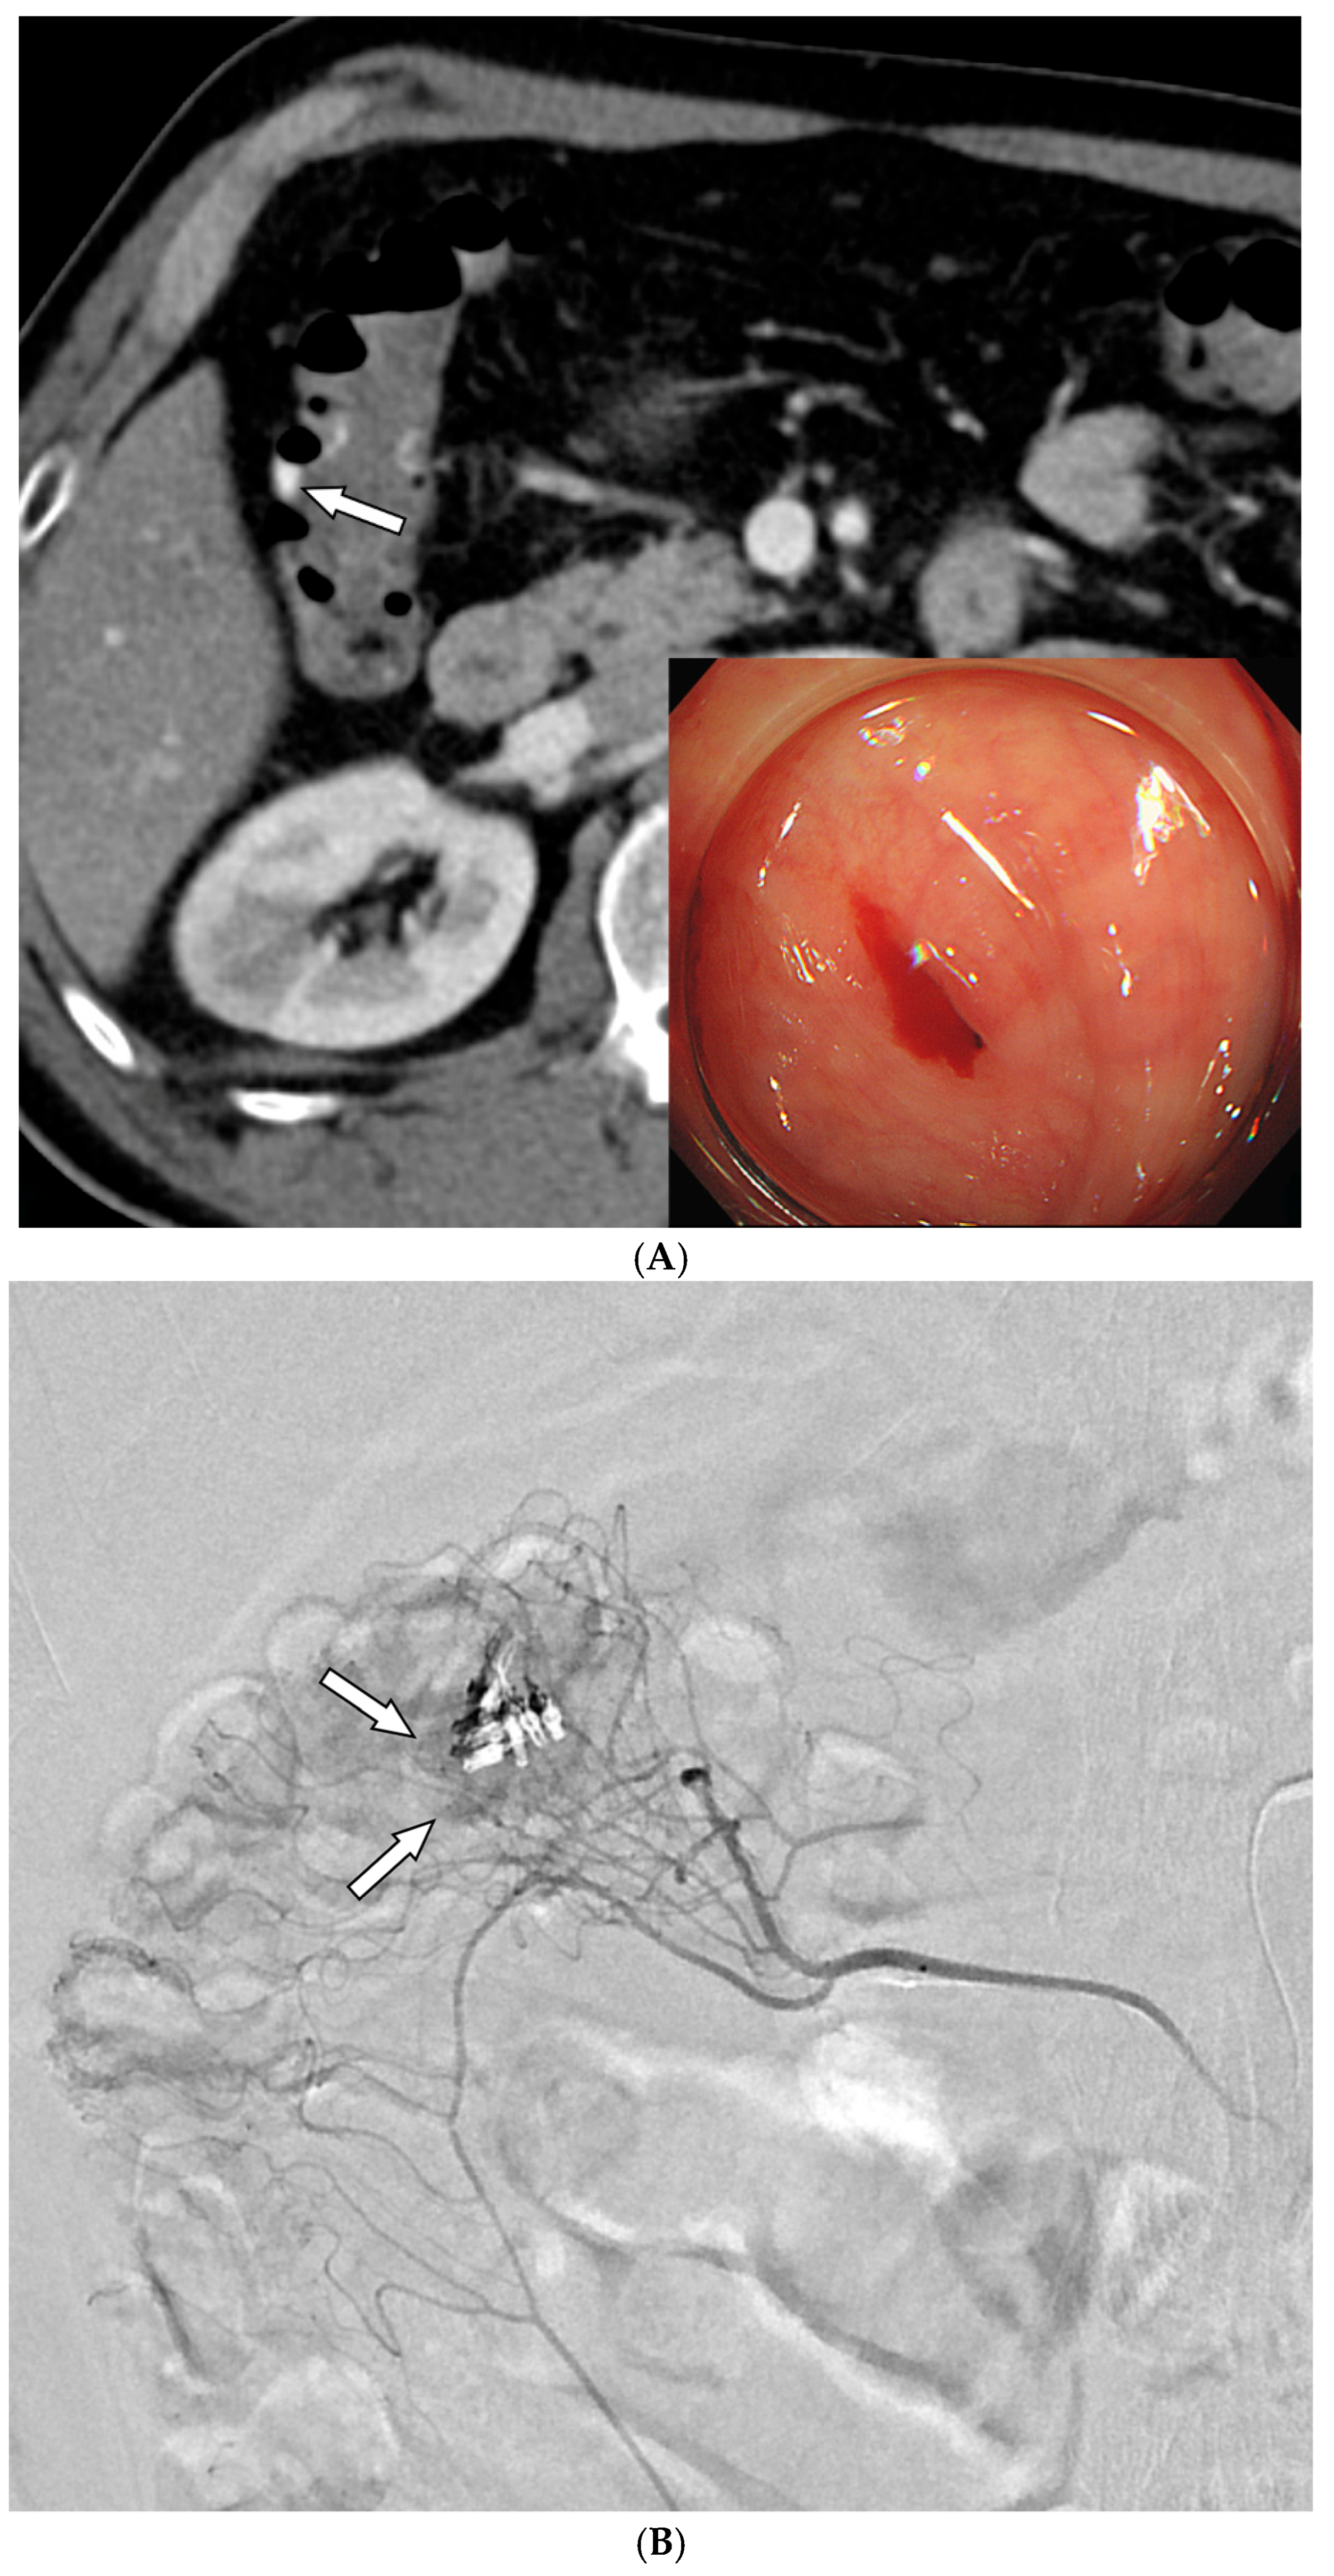

- Alali, M.; Cao, C.; Shin, J.H.; Jeon, G.; Zeng, C.H.; Park, J.-H.; Aljerdah, S.; Aljohani, S. Preliminary report on embolization with quick-soluble gelatin sponge particles for angiographically negative acute gastrointestinal bleeding. Sci. Rep. 2024, 14, 6438. [Google Scholar] [CrossRef]

| 7/F/70 | Uncertain | Superior rectal a. | No bleeding | QS-GSPs (350–560 μm) | Persistent | No | Improved, transient ischemic colitis 1 day later |